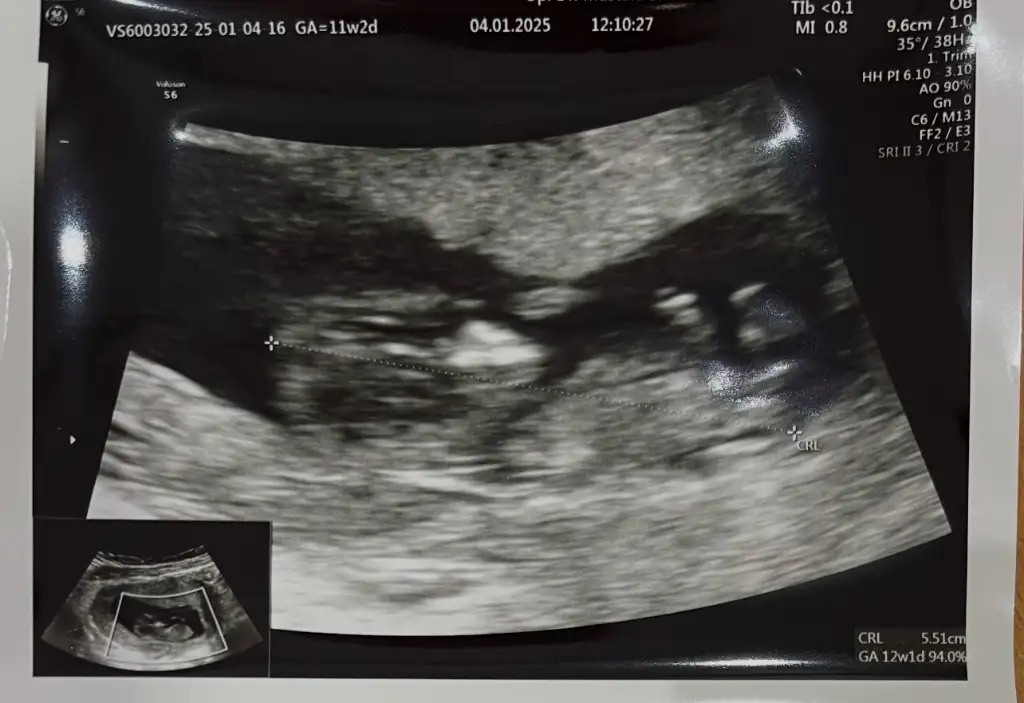

Bana da yorum yapar mısınız acaba 11+2 haftalık rica etsem?bence kız

Bana da yorum yapar mısınız acaba 11+2 haftalık rica etsem?Ben erkeğe benzettim ama emin değilim

Bana da yorum yapar mısınız acaba 11+2 haftalık rica etsem?Erkek gibi benzettim ama tabii emin değilim canım

Kıza benzettim benBana da yorum yapar mısınız acaba 11+2 haftalık rica etsem?